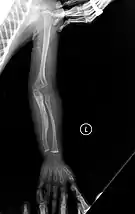

Although there is no cure,[10] most cases of OI do not have a major effect on life expectancy,[1]: 461 [15] death during childhood from it is rare,[10] and many adults with OI can achieve a significant degree of autonomy despite disability.[18] Maintaining a healthy lifestyle by exercising, eating a balanced diet sufficient in vitamin D and calcium, and avoiding smoking can help prevent fractures.[19] Genetic counseling may be sought by those with OI to prevent their children from inheriting the disorder from them.[1]: 101 Treatment may include acute care of broken bones, pain medication, physical therapy, mobility aids such as leg braces and wheelchairs,[10] vitamin D supplementation, and, especially in childhood, rodding surgery.[20] Rodding is an implantation of metal intramedullary rods along the long bones (such as the femur) in an attempt to strengthen them.[10] Medical research also supports the use of medications of the bisphosphonate class, such as pamidronate, to increase bone density.[21] Bisphosphonates are especially effective in children,[22] however it is unclear if they either increase quality of life or decrease the rate of fracture incidence.[7]

Metal rods can be surgically inserted in the long bones to improve strength, a procedure developed by Harold A. Sofield when he was Chief of Staff at Chicago's Shriners Hospitals for Children, a hospital that offers orthopedic care and surgery to children regardless of their family's ability to pay.[115] Large numbers of children with OI came to Shriners, and Sofield experimented with various methods to strengthen their bones.[116] In 1959, with Edward A. Millar [sic], Sofield wrote a seminal article describing a three-part surgery that seemed radical at the time: precisely breaking the bones ("fragmentation"), putting the resulting bone fragments in a straight line ("realignment"), then placing metal rods into the intramedullary canals of the long bones to stabilize and strengthen them ("rod fixation").[117] His treatment proved useful for increasing the mobility of people with OI, and it has been adopted throughout the world—it became standard surgical treatment for severe OI by 1979, in which year David Sillence found that ≈2⁄3 of the patients he surveyed with OI type III had undergone at least one rodding surgery.[42]: 108

Rodding surgery is often done with the hope that it will offer a path to ambulation, walking, to patients with moderate or severe OI. A 2020 review in The Journal of Bone and Joint Surgery (JB&JS) found it remains broadly popular: ≈2⁄3 of people with OI types III and IV (severe OI) have undergone some form of rodding surgery in their lives, at a mean age of 4+1⁄10 and 7+1⁄2 years respectively;[25]: Table I one possible explanation for a tendency towards earlier intervention in type III is that one half of affected children could not walk at all without the surgery, as their limbs were more bowed, so surgery was sought sooner.[25]

In those with type III OI who had undergone rodding surgery, 79.5% had the femurs and tibias of both legs rodded.[25]: Table I The most common form of rods used are intramedullary (IM) rods, some of which, such as the Fassier–Duval IM rod, are telescoping, meaning that they are designed to grow as the child grows, in an attempt to avoid the necessity of revision surgeries.[118] Telescoping IM rods are widely used,[119] and the common Fassier–Duval IM rod is designed to be used to rod the femur, tibia, and humerus.[120]: 1 The surgery involves breaking the long bones in between one and three (or more)[119]: Figure 4 places, then fixing the rod alongside the bone to keep it straight.[120]: 11